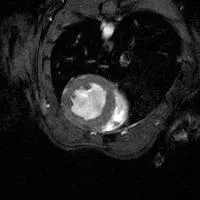

mouse heart 2-chamber cine MRI

2-chamber view

By synchronising rapid imaging with the cardiac cycle it is possible to generate “movie” sequences from which information can be obtained about the function of the heart. Images can be acquired in any orientation, but usually they are acquired in the short-axis, 2- and 4-chamber views. Standard cardiological parameters such as left ventricular volume, ejection fraction and cardiac output can be determined. Contrast agents enable the progression of myocardial infarcts to be monitored in longitudinal studies.

A Gadolinium contrast agent can be used to measure infarct size (pale grey myocardium). Images at twelve different phases of the cardiac cycle are acquired in approximately 3 minutes (Images courtesy of Jansen lab and Gray lab).